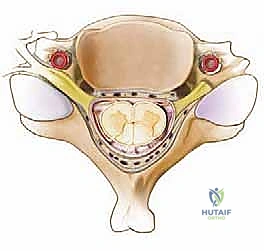

FIG 1 • Anatomy of cervical vertebrae.

FIG 1 • Anatomy of cervical vertebrae.

Let's review the critical anatomy we'll encounter. The cervical spine comprises seven vertebrae, normally arranged in a lordotic curve.

* C1 (Atlas) and C2 (Axis): These unique vertebrae are responsible for significant neck flexion-extension (occiput-C1, 50%) and rotation (C1-C2, 50%). We typically operate on the subaxial spine (C3-C7) for laminoplasty.

* Subaxial Vertebrae (C3-C7): These segments articulate posteriorly via zygapophyseal (facet) joints and laterally via the uncovertebral joints (joints of Luschka). Below C2-C3, lateral bending is coupled with rotation due to the 45-degree inclination of the cervical facet joints.

* Intervertebral Discs: Located between C2-C7 vertebral bodies, composed of an inner nucleus pulposus and outer annulus fibrosus.

* Spinal Canal Boundaries:

* Anteriorly: Vertebral bodies, intervertebral discs, and the posterior longitudinal ligament (PLL).

* Laterally and Posteriorly: The vertebral arch (pedicles, laminae, lateral masses).

* Posteriorly: The ligamentum flavum, which runs from the anterior surface of the superior lamina to the posterior surface of the inferior lamina.